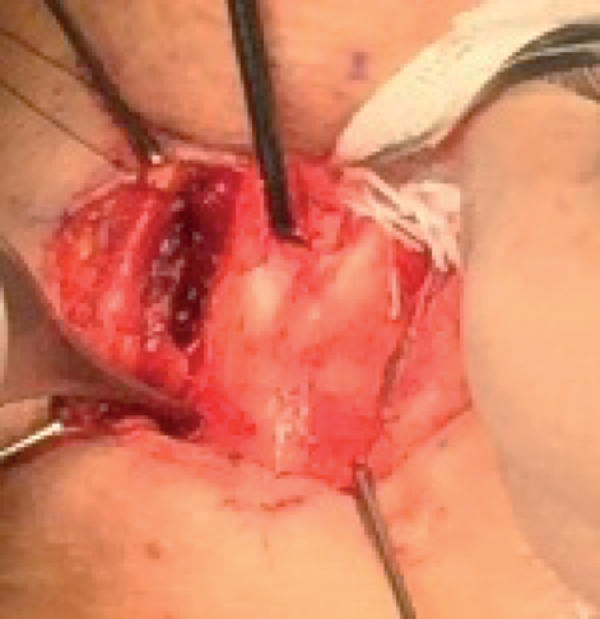

Exposure of thyroid laminae

Carefully separate the strap muscles in the midline. Meticulous haemostasis is necessary. Expose the two thyroid laminae from the notch superiorly down to the lower border of the thyroid lamina inferiorly. Put a 3/0 nylon through each side of the thyroid notch as stay suture for retraction (Figure 8).

Figure 8: top) Exposure of thyroid laminae, bottom) retraction suturing.